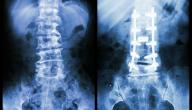

يطّلع الطبيب على أعراض الكسر وهي: التورّمات، والاحمرار، والألم، والتشوّهات في مَكان الكَسر، وتتواجد فتحات في الجلد حسب نوع الكسر. بالنسبة للأشعة السينية يطّلع الطبيب على الصورة للتأكّد من عدم وجود انقطاع باستمراريّة العظم، وعليه التأكّد هل هو كسر بسيط أم مُعقّد، وهل هو داخل المفصل أو خارجه، وهل هو دَاخل مَناطق النموّ أم لا وذلك ليتمّ تحديد طريقة العلاج.

الصور الشعاعية

هي صُور طبقيّة محوريّة، وذلك ليَستطيع الطّبيب أن يرى تفاصيل الكسر ليتم تحديد طريقة العلاج. عند وجودِ إصاباتٍ في الأربطة أو الغضاريف يضطرّ الطّبيب أحياناً لإجراء الرنين المغناطيسي لتَحديد طُرق العِلاج المناسبة.